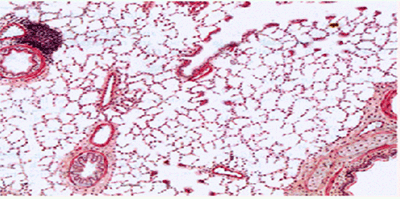

中山大学肿瘤防治中心病理科主任展示的活检切片显示,00后患者的肺癌细胞中:

· 铬含量超正常肺组织520倍(来自汽车刹车片磨损)

· 苯并芘-DNA加合物检出率达89%(强致癌物标志)